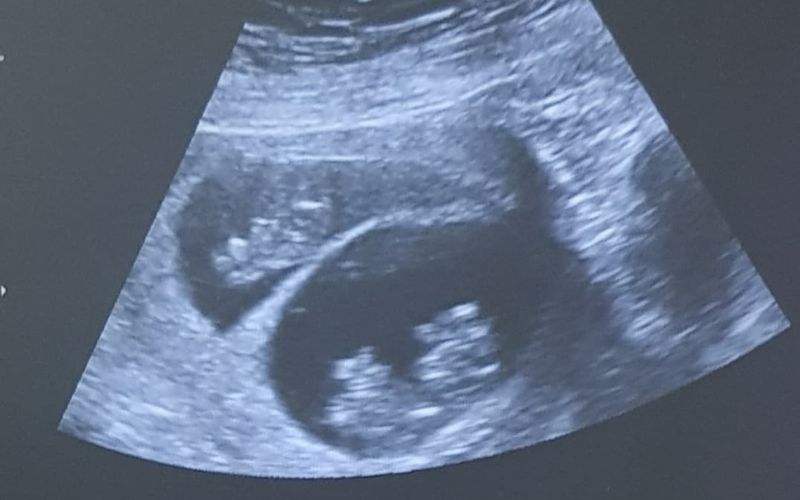

A few weeks passed, eventually the pain was gone, and I was sick… SO sick! It was worse than the food poisoning I’d had in South Africa after eating dodgy sushi. It was worse than the few times I’d accidentally finished several bottles of red wine. My eyes opened on a Wednesday morning and I ran straight for the toilet to throw up. After that I threw up in the shower, in the toilet again, and in the garden on my way out the door. Without wanting to get too excited, Ross and I went back for another scan. The stenographer roamed my belly, silently, for a long time. And I waited – not upset or excited – I couldn’t let myself feel any emotions, I just needed to prepare myself. I needed to be ready for anything. Finally, she turned the screen around to face me.

“I guess I should put you out of your misery,” she said. “You have two healthy babies.”

“No really,” she laughed. “You have two babies. See those two fluttering dots – that’s two heart beats.”